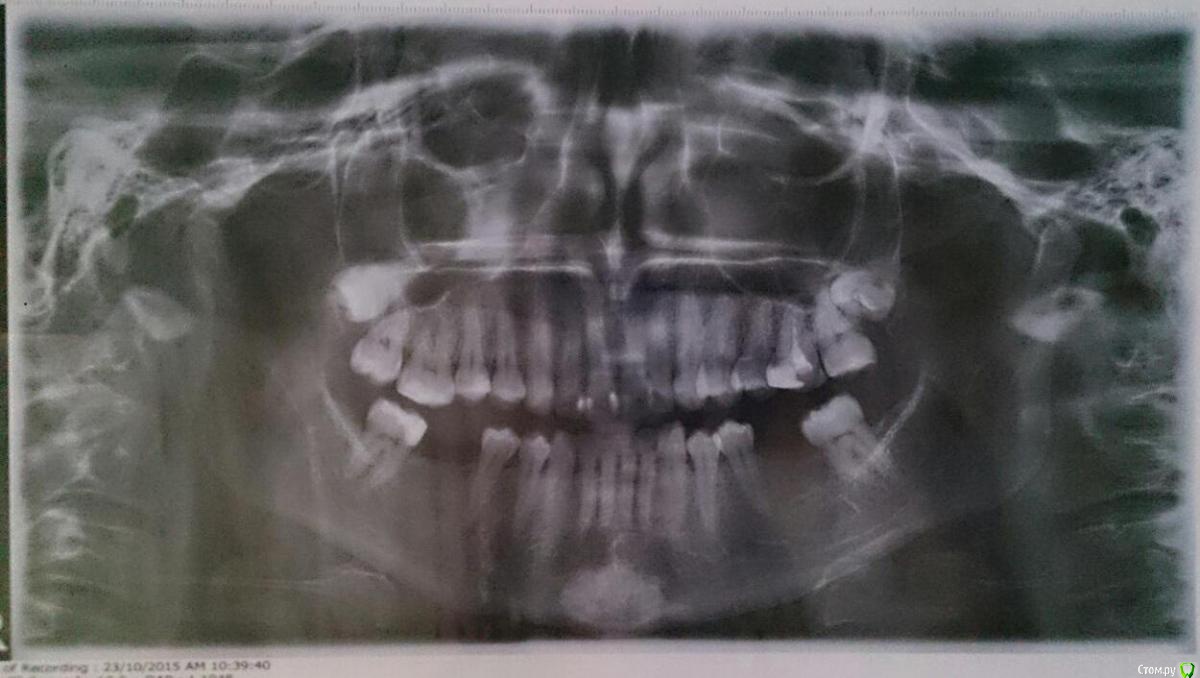

OkeOki Опубликовано 23 октября, 2015 Поделиться Опубликовано 23 октября, 2015 Всем привет! Хотелось бы исправить передний зуб и поставить недостающие нижние зубы. Очень нужен совет, с чего начинать лечение и как его продолжать? Кто как видит план лечения? Вообще хочу послушать советы специалистов по поводу моей ситуации Спасибо! Ссылка на комментарий

DR.P Опубликовано 23 октября, 2015 Поделиться Опубликовано 23 октября, 2015 (изменено) Я как ортопед порекомендовал бы сначала пройти ортодонтическое лечение, а затем уже протезироваться. Таким образом вы получите идеальный зубной ряд и отсутствие будущих проблем с возрастом. Зубы гораздо дольше служат, когда правильно распределена жевательная нагрузка, поэтому прикус играет ключевую роль! Только после расчета диагностических моделей, ТРГ, осмотра можно спланировать ваше лечение. Зубы мудрости на удаление. Изменено 23 октября, 2015 пользователем DR.P 3 Ссылка на комментарий